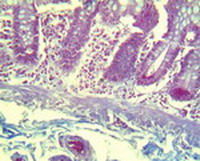

Աղիքի լորձաթաղանթի հետազոտությամբ հայտնաբերվում է ծածկող էպիթելի դեսքվամացիայի մասեր, որոնք երևում են էրոզիաների տեսքով՝ մերկացնող լայնացած մազանոթային ցանցով ենթալորձային շերտը (նկ. 1):

Նկար 1. Աղիների ծածկող էպիթելի դեոքվամացիա` էրոզիվ մակերեսների առաջացմամբ: Հեմատոքսիլին և էոզին |